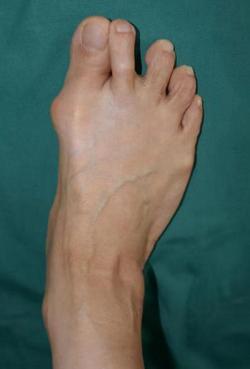

47岁的刘大姐家住泉山区,刘大姐出生时就被家人发现有双足踇指外翻畸形,大人觉得长大些可能会有改善,没重视;但随着年龄增长刘大姐双足的畸形不断加重,7个月前,刘大姐的右足开始疼痛,走路时间稍长或站久些便感觉疼痛难忍,一段时间的保守治疗无效,疼痛反而有加剧趋势。

7月11日,刘大姐来到足踝外科专家门诊,找到了足踝科大科主任、副院长石荣剑。石院长安排刘大姐做完体检和相关影像检查后,确诊刘大姐为先天性右足踇外翻畸形,决定为患者实施微创踇外翻矫正术。

很快,石院长为患者进行了右足踇外翻矫形术。麻醉师采用超声引导下神经阻滞,石院长周吉医生通过不到一厘米切口,在第1跖趾关节胫侧利用4毫米进口超声磨锯微创截骨,1个多小时,再次完美修整踇外翻。